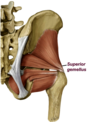

Superior Gemellus Muscle

- ischial spine–> medial side greater trochanter

- N. to obturator internus

- Lateral hip rotation

a deep gluteal muscle